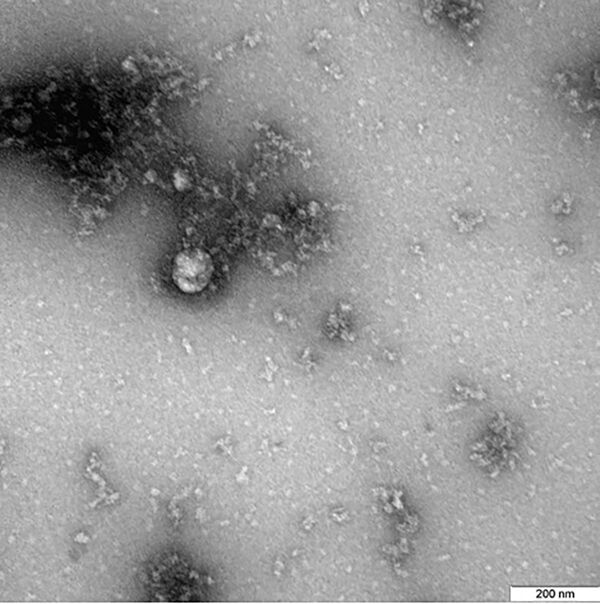

英コロナ変異株 ロシアの研究機関が初めて「撮影」

ロシア連邦消費者権利保護・福祉監督庁付属の国立研究センター「ベクター」は、2020年12月に患者から分離された新型コロナウイルスのいわゆる「英国型」を初めて撮影した。同庁がウェブサイトで発表している。

そのサイトによると、ウイルスの写真は、新型コロナウイルスの「英国型」の特性に関する研究の一環として顕微鏡で撮影された。